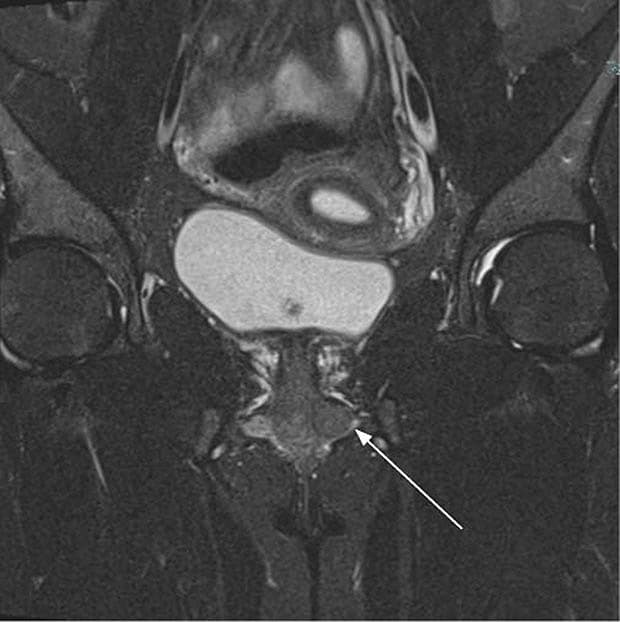

en ca. 1 cm stor rund, uøm og mobil udfyldning på venstre labia minora med tæt relation til urethra. Hun havde gener i form af dyspareuni og fremmedlegemefornemmelse, men ingen øvrige symptomer fra urinvejene. Der blev foretaget en MR-skanning af det lille bækken, hvor man på de vægtede billeder så et parauretralt leiomyom.